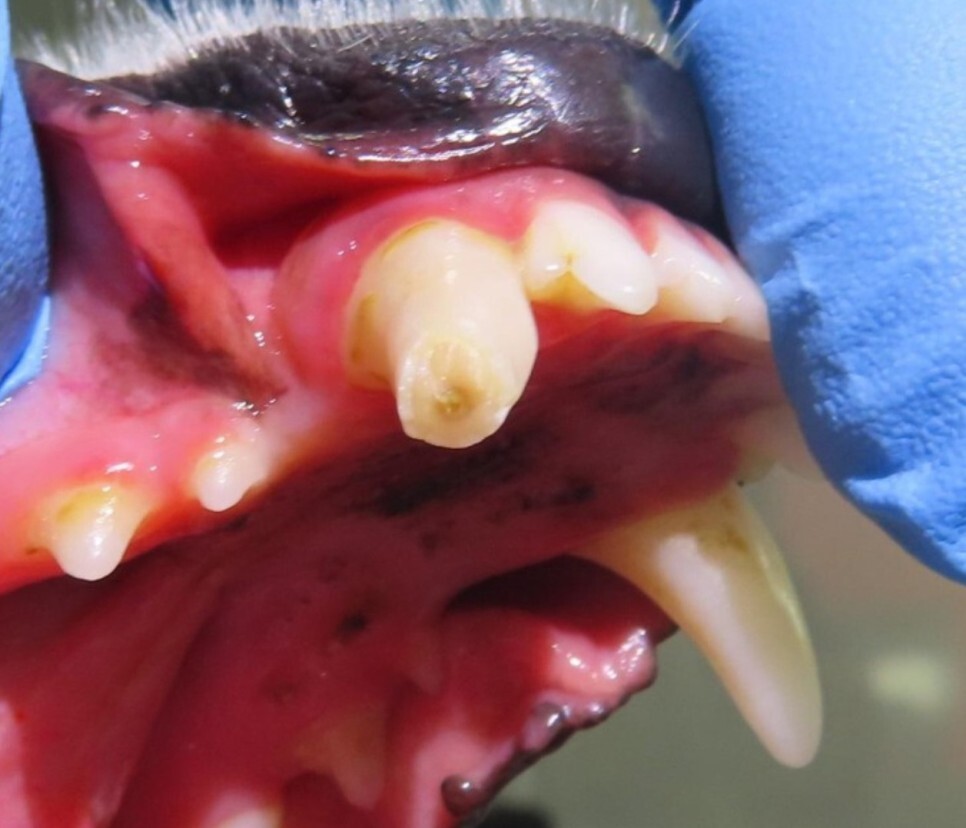

오늘은 아래턱 송곳니 골절로 인해 신경(근관)

치료를 진행한 아이 사례를 소개해 드리겠습니다.

치아가 군데군데 깨져있는 것은 알고 계셨으나

치수가 노출된 것을 발견하고 내원을 하셨습니다.

치아 내부에는 신경과 혈관이 지나가는 통로가

있습니다.

이러한 신경관이 손상을 받아 노출이 되면 구강 내

세균이 치조골 쪽으로 이동하여 염증을 유발합니다.